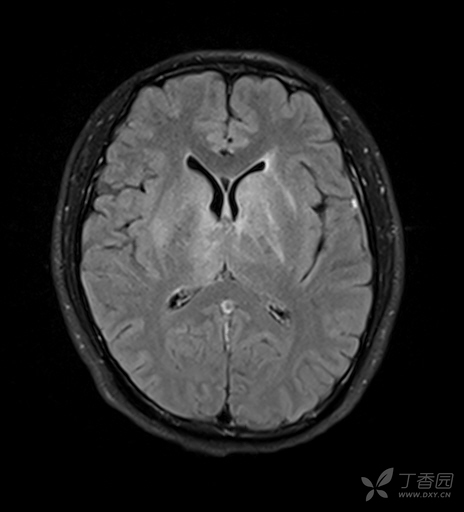

大家帮我看个片子

图片尺寸3008x2000